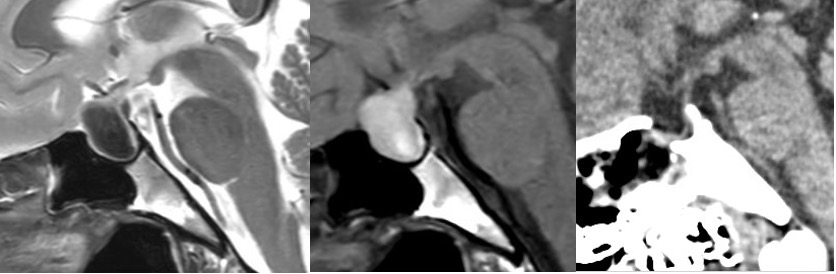

260331 60歳男性 頭蓋咽頭腫を開頭で摘出しました。